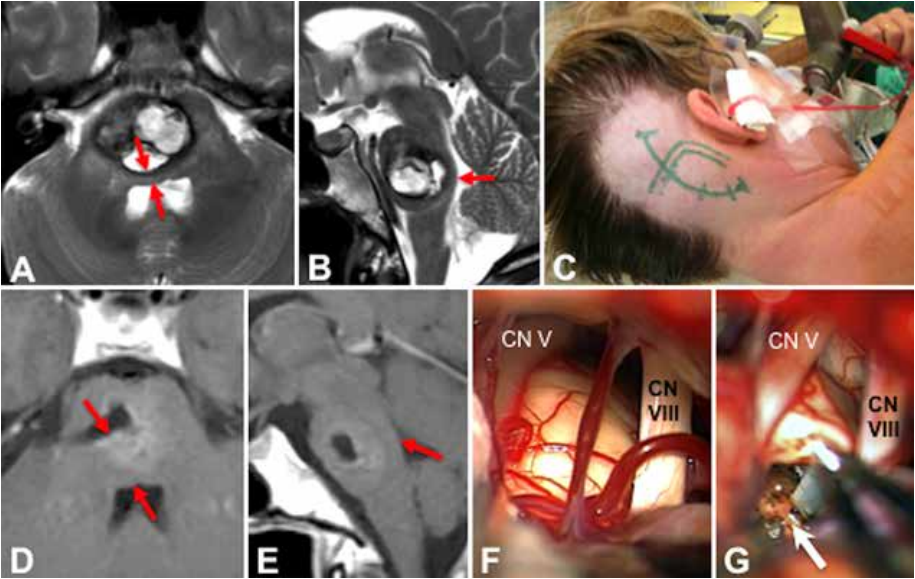

16岁男性,左侧感觉运动综合征和核间性眼肌麻痹。尽管病变相当大且靠近面神经,患者暂未出现面瘫

A和B:患者术前MR示脑干病变

C和D:患者接受了显微手术切除,该患者属于B型桥脑海绵状血管瘤,其在半坐位(C)通过纵向直线皮肤切口进行中线枕下开颅手术(D)。

E和F:术后轴向(E)和矢状增强(F)T1加权MR图像显示脑桥病变的完全切除,该桥脑海绵状血管瘤是通过背中线入路进行切除。

G:术中检查菱形窝膜暴露后,这个出血性桥脑海绵状血管瘤已经突出了第四脑室底部的距离5-6毫米。使用电生理刺激探针(白色箭头)确定双侧面神经的位置和范围。

H:在这张术中照片中记录了桥脑海绵状血管瘤的完全切除,该照片显示了包含毫米级的术后残腔,更上方是外侧导水管(白色箭头)。面部丘脑电刺激(蓝色箭头)在手术结束时监测效果产令人满意。因此,没有术后面瘫,这位年轻的患者在经历了平稳的术后过程,最后迅速康复如常生活。